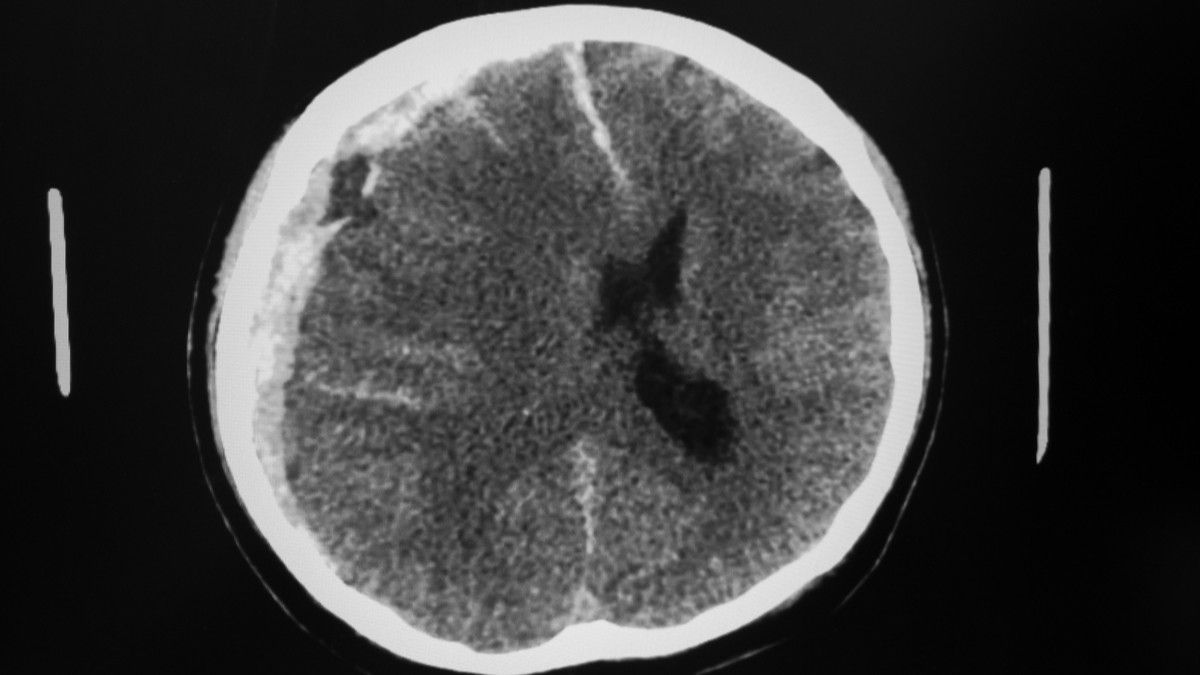

Hematoma subdural (SDH atau subdural hematoma) merupakan perdarahan di antara lapisan otak, yakni lapisan arachnoid dan lapisan dura (meningeal).

"Ada tiga tipe SDH berdasarkan waktunya, yaitu SDH akut, SDH subakut, dan SDH kronis. SDH akut terjadi kurang dari 72 jam, SDH subakut 3-7 hari setelah cedera, dan SDH kronis terjadi dalam beberapa minggu," ungkap dr. Sepriani Timurtini Limbong.

"Penanganannya tergantung derajat keparahan. Biasanya akan dilakukan pemeriksaan dulu, seperti MRI atau CT scan. Kemudian, ditentukan apakah harus dilakukan pembedahan atau ada pilihan lain," ungkap dr. Sepriani.